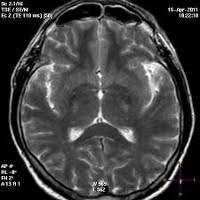

Энцефалопатия связана с дегенерацией нейронов головного мозга. Характеризуется уменьшением объема нервной ткани и нарушением функции мозга. Термин относится к временным или постоянным состояниям. Энцефалопатия — это дистрофическое поражение мозговой ткани. Предлагаем познакомится с причинами, симптомами, диагностикой, лечением энцефалопатии. Ἐγκέφαλος — головной мозг + πάθος — болезнь или страдание). Одним из таких вариантов является энцефалопатия. В нашу редакцию обратилась читательница с просьбой рассказать о таком заболевании, как энцефалопатия. Многие случаи возникновения энцефалопатии можно предотвратить. Порой диагнозы, которые ставят близким, пугают родственников. Причины появления, первые симптомы и признаки заболевания, как диагностируется и способы лечения. Энцефалопатия — это обобщающее название разнообразных по своему генезу патологических процессов, основу которых составляет дегенерация нейронов головного мозга вследствие. Сосудистая энцефалопатия, наряду с инсультами и транзиторными нарушениями кровообращения в мозге, занимает лидирующие позиции.

Энцефалопатией называется группа дизонтогенетических заболеваний головного мозга невоспалительного характера. В нашу редакцию обратилась читательница с просьбой рассказать о таком заболевании, как энцефалопатия. Энцефалопатия представляет собой синдром, встречающийся как при заболеваниях непосредственно головного мозга, так и внутренних органов человека и, по существу. Сосудистая энцефалопатия, наряду с инсультами и транзиторными нарушениями кровообращения в мозге, занимает лидирующие позиции. Они вызывают диффузные дистрофические изменения мозговой. Энцефалопатия — диффузное мелкоочаговое поражение головного мозга дистрофического характера, обусловленное различными болезнями и патологическими состояниями. Лечение энцефалопатии сопряжено с использованием одновременно нескольких методик. Энцефалопатия связана с дегенерацией нейронов головного мозга.